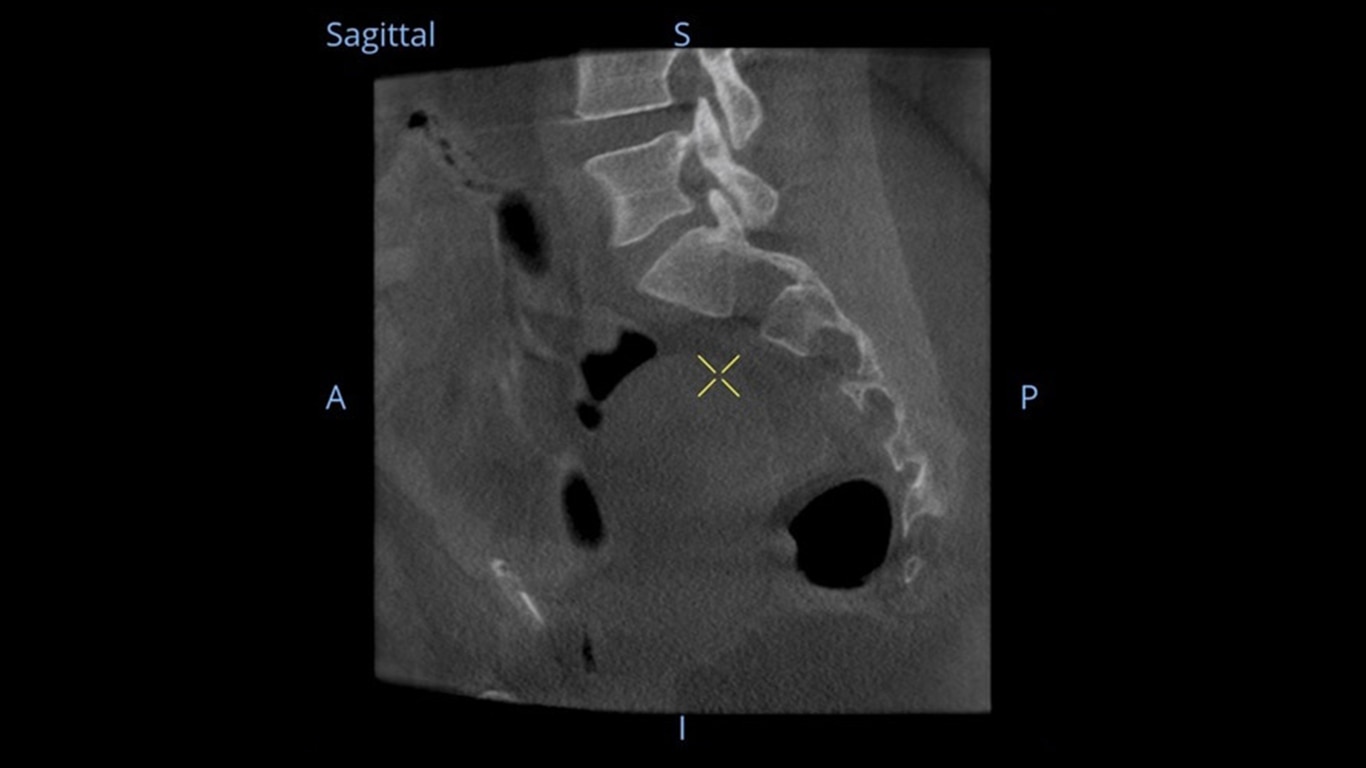

Mehr sehen, schneller entscheiden: Der OEC 3D ermöglicht die gleichzeitige Darstellung mehrerer Ebenen bei verschiedensten Anwendungen. Ob Spondylodesen, komplexe Trauma- Chirurgie oder Bronchoskopien. Mit einem Volumen von 19 × 19 × 19 cm liefert er bis zu 67 % mehr Bildinformationen als vergleichbare Systeme – für mehr Sicherheit und Effizienz im OP.

Analysieren Sie Ihre Scans mit dem GE Volume Viewer – genauso intuitiv wie am CT. Profitieren Sie von der vollständigen Darstellung axialer, koronarer und sagittaler Ebenen sowie von MIP-Ansichten und 3D-Visualisierungen im VR-Modus. Scrollen Sie durch bis zu 512 Schichten mit nahtloser Anpassung der Schichtdicke – für eine präzise Befundung direkt im OP.